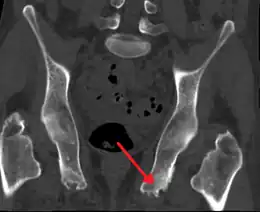

Enthésopathie du bassin probablement due à une spondylarthrite ankylosante

Une enthésiopathie ou enthésopathie est une inflammation d'une enthèse. Les enthèses sont les zones où s'insèrent sur les os les capsules articulaires, tendons et ligaments.

L'origine de cette pathologie peut être traumatique (par exemple accident de voiture avec coup du lapin) ou dégénératif dans le cadre de maladies articulaires chroniques évolutives ou non (du genre polyarthrite rhumatoïde ou spondylarthrite ankylosante).